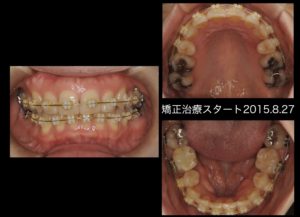

矯正開始2ヶ月。犬歯の角度が改善され、まだぎこちないが下顎が左右に動かせるようになった。

矯正治療終了後。前歯部の咬合も良好。犬歯誘導も確立できている。夜間のマウスピースは必須である。